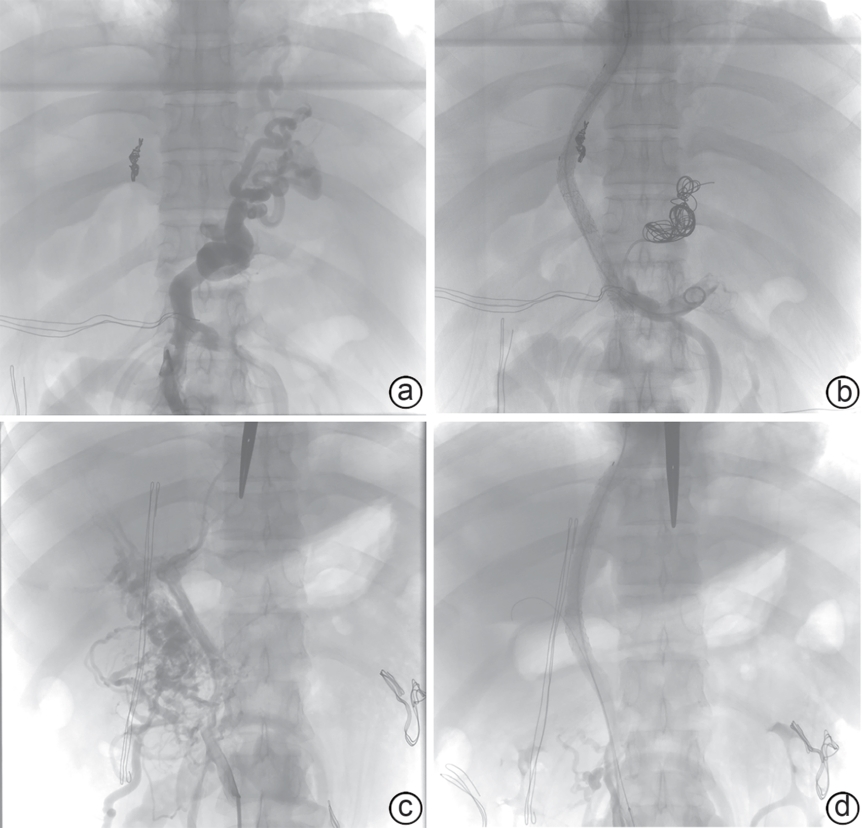

外科辅助经颈静脉肝内门体分流术治疗门静脉高压合并复杂门静脉血栓的效果及安全性分析

范振华, 董成宾, 李其美, 张裕, 吴一凡, 刘东方, 许光中, 王德仲, 陈建飞, 岳振东, 王磊

2026, 42(3): 586-592. DOI: 10.12449/JCH260313

摘要:

目的  探讨外科辅助经颈静脉肝内门体分流术(SA-TIPS)在门静脉高压合并复杂门静脉血栓(包括门静脉海绵样变)治疗中的可行性、安全性及疗效。  方法  选取2023年11月—2025年1月首都医科大学附属北京世纪坛医院收治的36例行SA-TIPS治疗的门静脉高压合并复杂门静脉血栓患者,统计并分析患者的一般情况、手术过程的技术资料(手术成功率、穿刺针数、手术时间、支架使用数量和分流道长度)、围手术期并发症及手术恢复情况等。比较分流术前后门静脉压力梯度(PPG)变化,计算PPG下降达标率和术后1周内支架通畅率。计量资料两组间比较采用配对样本t检验。  结果  36例患者中,34例(94.4%)成功实施SA-TIPS。围手术期并发症发生率为16.7%(6/36),包括胸腹腔出血3例,术中心律失常2例,切口感染1例。SA-TIPS分流后PPG较术前显著下降(t=19.85,P<0.01),其中PPG下降幅度≥50%的患者占76.5%(26/34),1周内影像学复查分流道通畅率为100%。  结论  SA-TIPS治疗合并复杂门静脉血栓(包括门静脉海绵样变)的门静脉高压具有技术成功率高、安全有效的优势,值得临床推广。